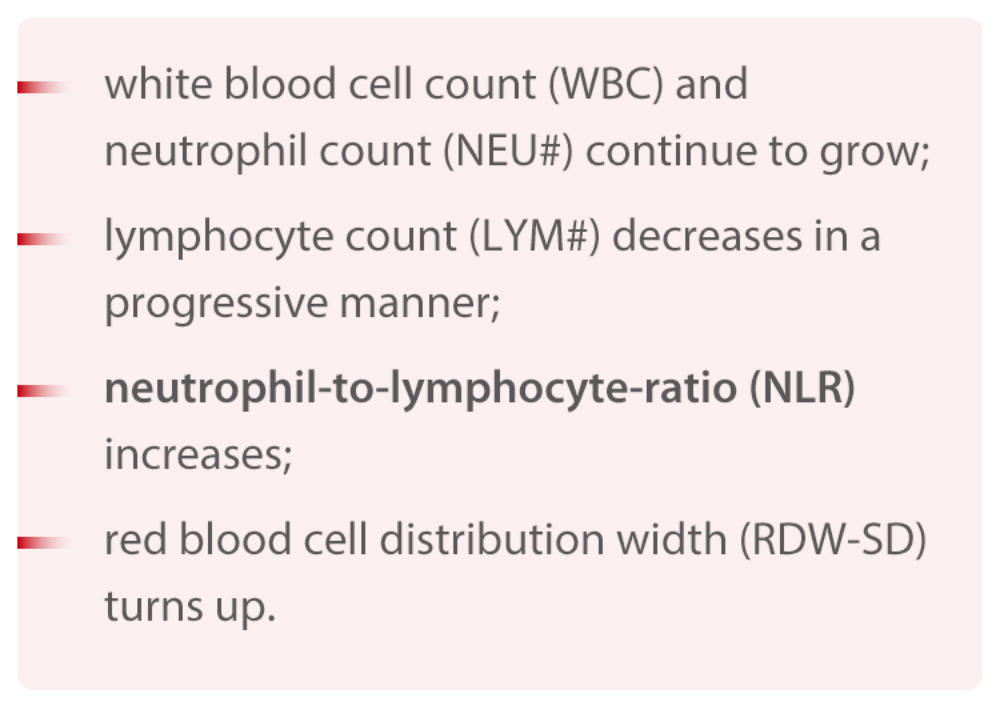

A. From the comparison between CBC tests from moderate and severe cases, it could be concluded that, as the patientвАЩs condition deteriorates, his or her:

This article studied the changes in CBC test results of 45 COVID-19 patients at different stages. The trend of LYM# is in line with the that described on the 6th Edition of Provisional Criteria for Diagnosis and Treatment of COVID-19. In addition, the research team led by Prof. Nanshan Zhong, member of the Chinese Academy of Engineering and prominent expert in respiratory diseases, has published a study on 1099 COVID-19 cases which shows that the proportional decline of lymphocyte reached 82.1%. [3]

For the NLR parameter, the result of this study corresponds with the trend described in the article, Neutrophil-to-Lymphocyte Ratio Predicts Severe Illness Patients with 2019 Novel Coronavirus in the Early Stage, a preprint published by Beijing Ditan Hospital on the medRxiv platform. [4] The paper points out that NLR can be used as a parameter to give early alert for possible acute health deterioration of COVID-19 patients.

With NLR and RDW-SD results in focus, a linear regression and ROC curve analysis were introduced in order to establish the NLR & RDW-SD parameter as an indicator to identify severe cases. With an AUC reaching 0.94, this parameter can provide useful information to help doctors decide which category the patient should be put into and what corresponding treatment the patient should receive. However, it must be pointed out that this is a retrospective study and its applicability has yet to be validated with more clinical cases.